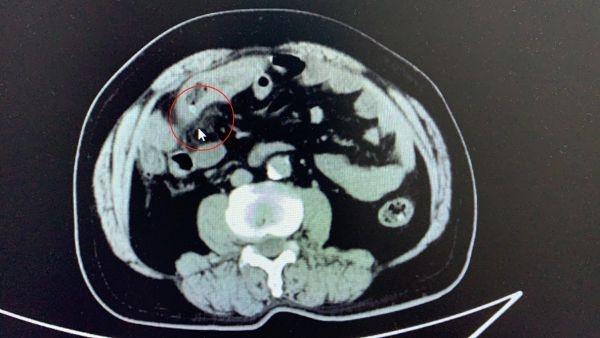

该院胃肠外科宋亚锋医生接诊后 , 为张先生进行了详细检查 , 发现患者小肠管壁水肿增厚 , 其中还有一个高密度影穿透了肠管管壁 , 抽血检查则显示张先生白细胞指标远超正常值 。 种种迹象表明 , 张先生可能不小心吞下了异物 , 并刺穿了小肠 , 导致出现穿孔、炎症 。

难道张先生不小心把骨头茬吞到肚子里了?手术探查发现 , 张先生小肠上确实有两个明显的破洞 , 肠道内的粪便、消化液也漏到腹腔 , 导致了腹腔感染 。 进一步检查发现 , 刺穿张先生肠道的并非骨头 , 而是一枚两头尖尖的枣核 。 医生为其切除破洞处大约7-8厘米的肠道 , 并反复冲洗污染的腹腔 , 手术顺利完成 。 目前张先生已转危为安 。